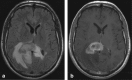

Background and purpose: The splenium of the corpus callosum is the most posterior part of the corpus callosum. Its embryological development, anatomy, vascularization, function, imaging of pathology, possible pathophysiological mechanisms by which pathology may develop and the clinical consequences are discussed.

Methods: A literature-based description is provided on development, anatomy and function. MR and CT images are used to demonstrate pathology. The majority of pathology, known to affect the splenium, and the clinical effects are described in three subsections: (A) limited to the splenium, with elaboration on pathophysiology of reversible splenial lesions, (B) pathology in the cerebral white matter extending into or deriving from the splenium, with special emphasis on tumors, and (C) splenial involvement in generalized conditions affecting the entire brain, with a hypothesis for pathophysiological mechanisms for the different diseases.

Results: The development of the splenium is preceded by the formation of the hippocampal commissure. It is bordered by the falx and the tentorium and is perfused by the anterior and posterior circulation. It contains different caliber axonal fibers and the most compact area of callosal glial cells. These findings may explain the affinity of specific forms of pathology for this region. The fibers interconnect the temporal and occipital regions of both hemispheres reciprocally and are important in language, visuospatial information transfer and behavior. Acquired pathology may lead to changes in consciousness.